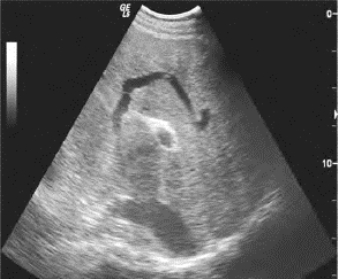

1.36.4四、腹腔大血管